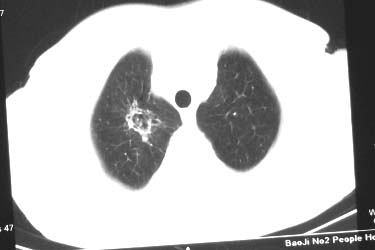

右肺中叶病灶境界基本清晰,肺窗上似见血管伸入,增强后明显强化,考虑动静脉瘘可能吧!

右肺中叶团片影,似多病灶融合而成,密度不均匀,边界清楚,周围见明显的索条及小结节,左肺亦见斑片影,纵隔窗未见肿大淋巴结.多考虑:肺内慢性炎性病变伴纤维化.

右肺中叶软组织块(挑剔一下纵隔窗窗宽不理想),其周围可见多个类圆形结节,右肺上叶尖段见斑片、索条状致影,左肺小结节。

1.右肺周围型肺癌伴肺内转移;

2.右肺上叶陈旧性结核;

3.左肺炎性结节;

右肺中叶软组织块,其周围可见多个类圆形结节,右肺上叶尖段见斑片、索条状致影,左肺小结节,见分叶、毛刺及胸膜凹陷征。1.左肺周围型肺癌伴右肺内转移; 2.右肺上叶陈旧性结核。